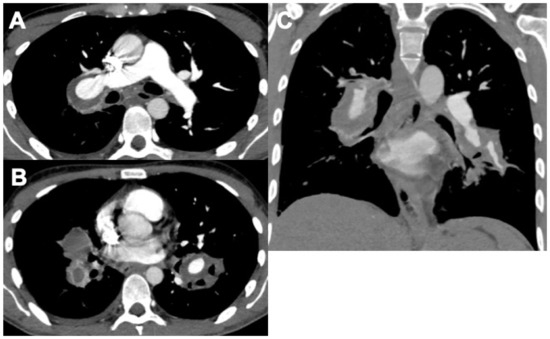

Behçet Disease (BD) and Hughes–Stovin Syndrome (HSS)

| Behçet disease (BD) |